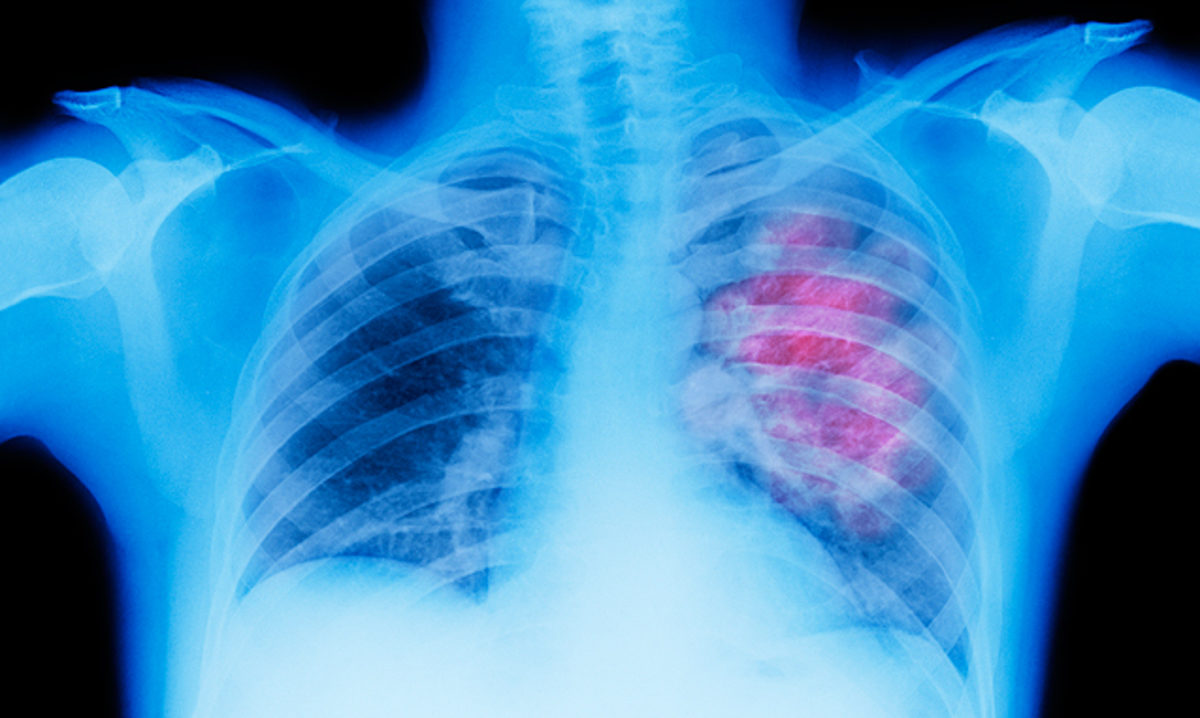

Mε επιτυχία πραγματοποιήθηκε στο νοσοκομείο ΥΓΕΙΑ η πρώτη στην Ελλάδα θωρακοσκοπική επέμβαση αφαίρεσης καρκίνου του πνεύμονα, χωρίς να χορηγηθεί γενική αναισθησία στον ασθενή, ο οποίος ήταν ξύπνιος με ελαφρά καταστολή.

Η επέμβαση εφαρμόστηκε σε ασθενή με καρδιολογικά προβλήματα και μειωμένη  αναπνευστική επάρκεια. Πρόσφατα είχαν γίνει επεμβάσεις βιοψίας πνεύμονα με την ίδια τεχνική, σε ασθενείς με επηρεασμένη αναπνευστική λειτουργία.